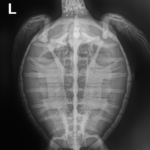

9.4 lbs. non -FP juvenile green

Patient Injuries

Hooked on left front flipper

In-house PCV = 30%, TP = 4.0 g/dl, glucose = 126. Started on Ceftaz, Vitamin B, and Normosol.